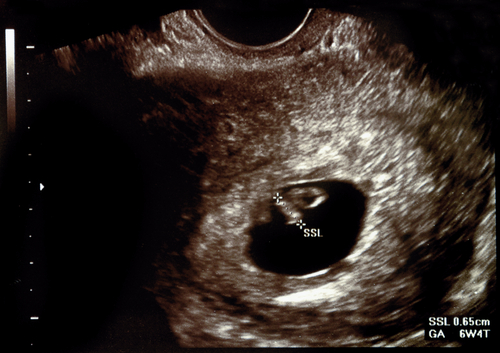

胎嚢は、赤ちゃんを包む膜のことです。エコー写真で見ると、ぽっかりと楕円形の黒い空間ができているのがわかります。妊娠が判明し、初期の検査でママが一番初めに目にすることができる、赤ちゃんの生存の証かもしれません。胎嚢は英語で「gestational sac」と言い、超音波検査の結果ではGSと表示されます。

胎嚢が確認できると、5週2日目までに胎嚢の中にさらに小さな丸いリングが出現します(※1)。リングの正体は「卵黄嚢(らんおうのう)」と呼ばれる組織です。卵黄嚢は胎盤ができるまで、成長に必要な栄養を供給したり血を作ったりする役割を担っています。

妊娠4週2日目の胎嚢は、直径が1.5mmととても小さいものです(※2)。しかし2日後の4週4日目になると倍以上の3.5mmほどの大きさにまで成長し、エコー検査でも検出されやすくなります。

妊娠5週0日(受精後21日)までは胎嚢の直径は1日に0.9mm、1週間で約7mmのスピードで成長するとされています。超音波断層法では、胎嚢の直径は0.70×妊娠週数-2.54(cm)であらわされます(※3)。とはいえ、月経周期や排卵日の計算が間違っていた場合は妊娠週数がずれることもあり、目安となるサイズに比べて実際の大きさが小さいこともあります。